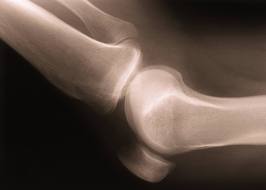

Knee Pain Traumatic: Initial Diagnosis and Management

- Radiographs to rule out fractures.